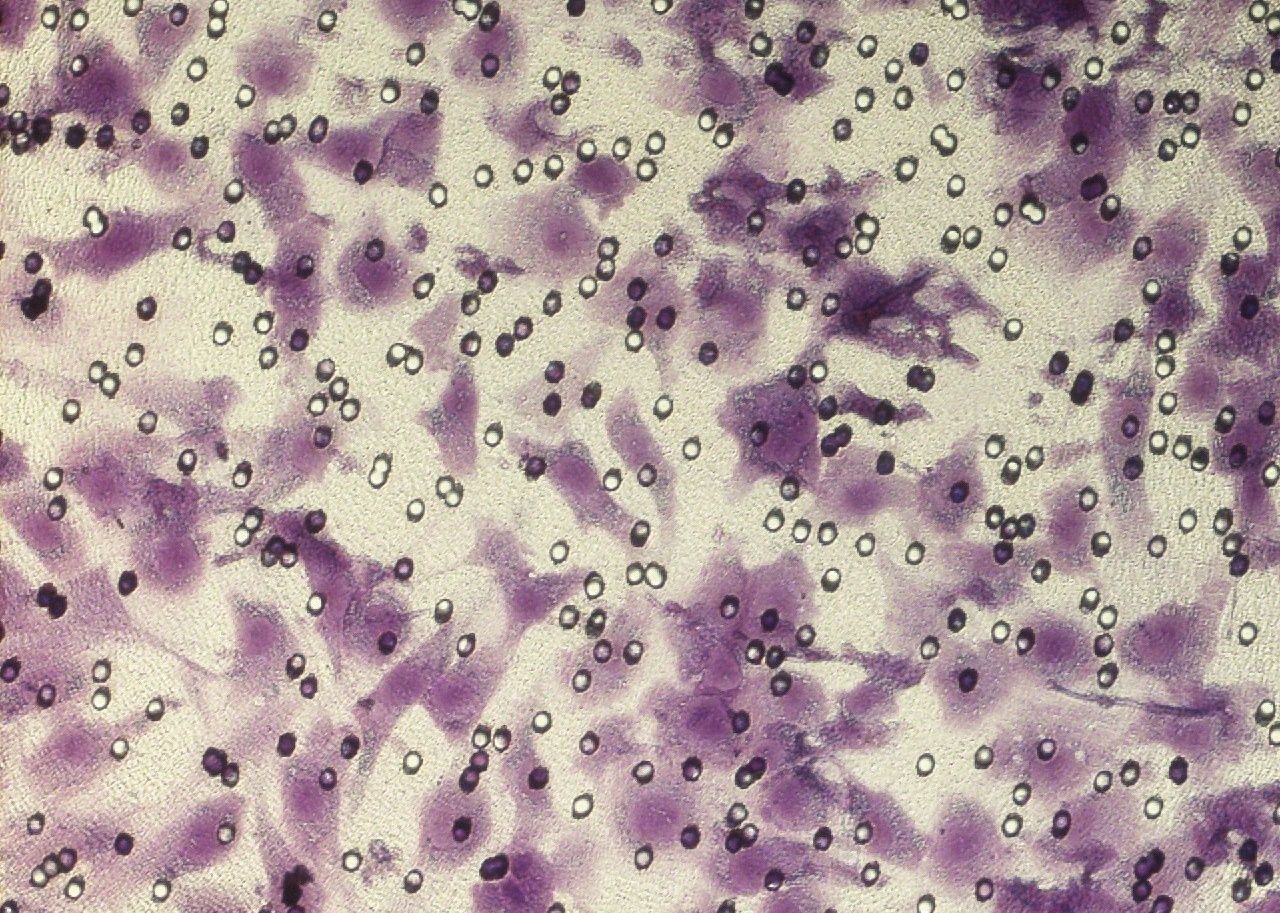

Transwell結果展示